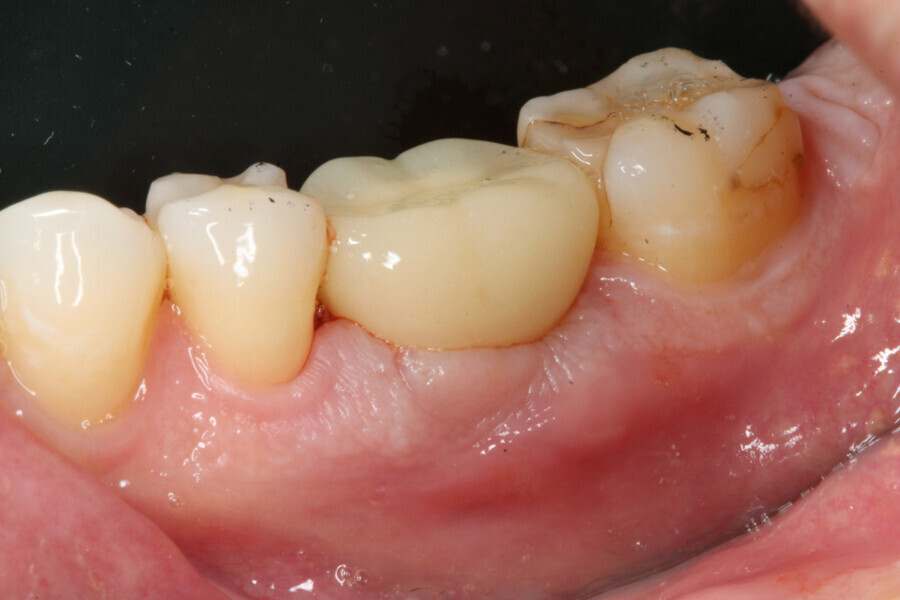

One week after implant surgery, healing was satisfactory and the abutment and provisional crown were inserted (Figs. 10–14).

During the healing period, the final crown was manufactured based on the Atlantis Core File. Eight weeks after implant placement, the soft tissue had healed well (Figs. 15 & 16) and was ready for the final zirconia crown (Fig. 17). Radiographic evaluation with the final restoration confirmed the successful outcome of the treatment (Fig. 18).